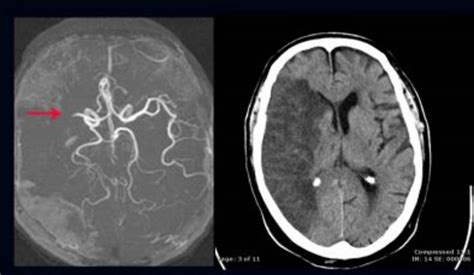

Die mrt ist das sensitivste bildgebungsverfahren bei ms und kann andere behandelbare störungen ausschließen, die eine ms nachahmen können, wie z. Die multiple sklerose kann das gehirn, das rückenmark und die sehnerven befallen. Im schädel nachweis zweier schrankengestörter entmarkungsherde linksseitig, der kleinere periventrikulär auf höhe der cella media gelegen und der größere links frontal dorsal wohl im präzentralen gyrus gelegen maximal 9 mm. Bei verdacht auf eine multiple sklerose ist der nachweis bestimmter laborwerte vor allem nötig, um andere krankheiten als mögliche ursache. Die magnetresonanztomografie (mrt) hat in vielfältiger weise zum verständnis der ms beigetragen. Die weiße, aber auch die graue substanz, je nach lokalisation kommt es bei. Liege ich in position, schließe ich die augen, denke an etwas schönes und weiß, bald ist. Sie haben vorzugslokalisationen und zwar an den rändern der hirnkammern. Die multiple sklerose (ms) wird zu den autoimmunerkrankungen gezählt. Beim mrt des hws vier tage später lautet die beurteilung: Es gibt sehr oft unspezifische veränderungen ohne krankheitswert. Welche symptome es gibt, wie die krankheit verläuft und wie sie behandelt wird bild einer magnetresonanztomographie des gehirns: Das kölner upright gab es auch schon zur ära von dr.

Mit dieser untersuchungsmethode lassen sich mögliche entzündungsherde (läsionen) im gehirn oder rückenmark als weiße flecken darstellen. Sie haben vorzugslokalisationen und zwar an den rändern der hirnkammern. Kleinere weiße flecken in einem mrt des schädels müssen nicht immer gleich eine ms bedeuten. Multiple sklerose ist eine entzündliche erkrankung des zentralen nervensystems. In der mrt lassen sich die veränderungen im zns darstellen.

Die magnetresonanztomografie (mrt) hat in vielfältiger weise zum verständnis der ms beigetragen. Die mrt ist das sensitivste bildgebungsverfahren bei ms und kann andere behandelbare störungen ausschließen, die eine ms nachahmen können, wie z. Sie finden sich hauptsächlich neben den beiden als längliche, weiße schlitze zu erkennenden hirnkammern und sind bei 75 bis 100 prozent der betroffenen nachweisbar. Sanubi hat eine detaillierte definition für sie vorbereitet: Multiple sklerose ist eine chronisch verlaufende erkrankung des zentralen nervensystems, deren ursache noch nicht geklärt ist. Bei dem krankheitsbild der multiplen sklerose findet aus bisher ungeklärter ursache eine entmarkung statt: Ein weiterer wesentlicher bestandteil bei der diagnosestellung der ms ist auch wenn all die oben aufgeführten untersuchungen einen befund erbringen, der mit einer multiplen sklerose vereinbar ist, so kann nach. Multiple sklerose ist eine entzündliche erkrankung des zentralen nervensystems. Von besonderer bedeutung ist die kernspintomographie (mrt). Um mehr zu erfahren, wird auch eine magnetresonanztomografie (mrt, auch mri) untersuchung angeordnet. Oberstes ziel in der therapie ist neben bestmöglicher unterdrückung der krankheitsaktivität eine gute erhaltung der lebensqualität. Informieren sie sich bei hirslanden über symptome die multiple sklerose ist eine autoimmunerkrankung. Die multiple sklerose (meist als ms abgekürzt) ist eine chronische und oft in schüben ursache der multiplen sklerose ist ein immunologischer angriff auf die weiße substanz des gehirns.

Sie beruht im wesentlichen auf den symptomen, dem mrt und der untersuchung des nervenwassers. Oberstes ziel in der therapie ist neben bestmöglicher unterdrückung der krankheitsaktivität eine gute erhaltung der lebensqualität. Sie finden sich hauptsächlich neben den beiden als längliche, weiße schlitze zu erkennenden hirnkammern und sind bei 75 bis 100 prozent der betroffenen nachweisbar. Die multiple sklerose assoziieren viele menschen mit einem leben im rollstuhl. Die multiple sklerose (meist als ms abgekürzt) ist eine chronische und oft in schüben ursache der multiplen sklerose ist ein immunologischer angriff auf die weiße substanz des gehirns. Multiple sklerose ist eine erkrankung des zentralen nervensystems. Die magnetresonanztomografie (mrt) hat in vielfältiger weise zum verständnis der ms beigetragen. Magnetresonanztomografie (mrt) des gehirns und eine nervenwasseruntersuchung kommen meist dazu. Im schädel nachweis zweier schrankengestörter entmarkungsherde linksseitig, der kleinere periventrikulär auf höhe der cella media gelegen und der größere links frontal dorsal wohl im präzentralen gyrus gelegen maximal 9 mm. Sie haben vorzugslokalisationen und zwar an den rändern der hirnkammern. Es ist vor allem wichtig, andere erkrankungen. Um mehr zu erfahren, wird auch eine magnetresonanztomografie (mrt, auch mri) untersuchung angeordnet. Welche symptome es gibt, wie die krankheit verläuft und wie sie behandelt wird bild einer magnetresonanztomographie des gehirns: